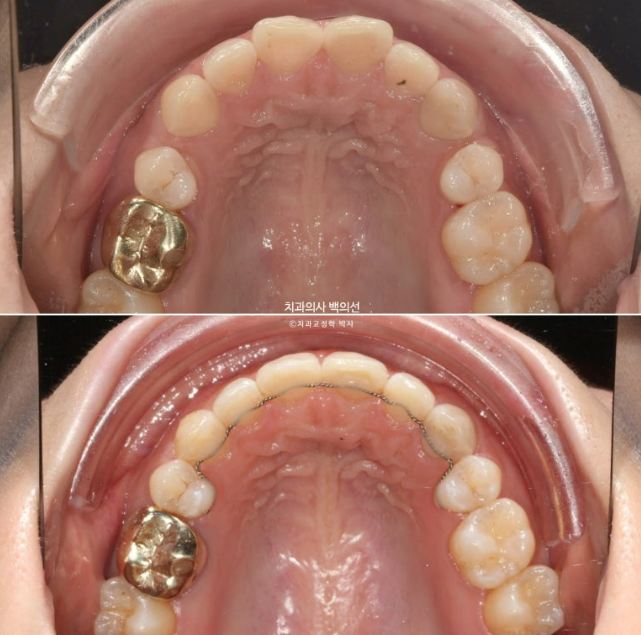

24.09

단 과개교합이 심해 투명장치만으로는 해결이 어려워 앞니쪽에 교정용 나사인 미니스크류를 심고 고무줄을 같이 사용했습니다.

24년 4월부터 9월까지 6개월간 14개 장치를 모두 낀 후 모습입니다.

과개교합은 개선이 되어 아래앞니가 보입니다.

발치공간도 대부분 없어졌으나 미세한 공간이 여전히 남아있습니다.

추가장치 한세트를 더 써서 과개교합을 더 개선하고 발치공간을 타이트하게 마무리짓기로 하고 재제작에 들어갑니다.

24.03~25.04

다시 벌어졌던 발치공간은 깔끔하게 닫았고 철사유지장치까지 붙여놓은 모습입니다.